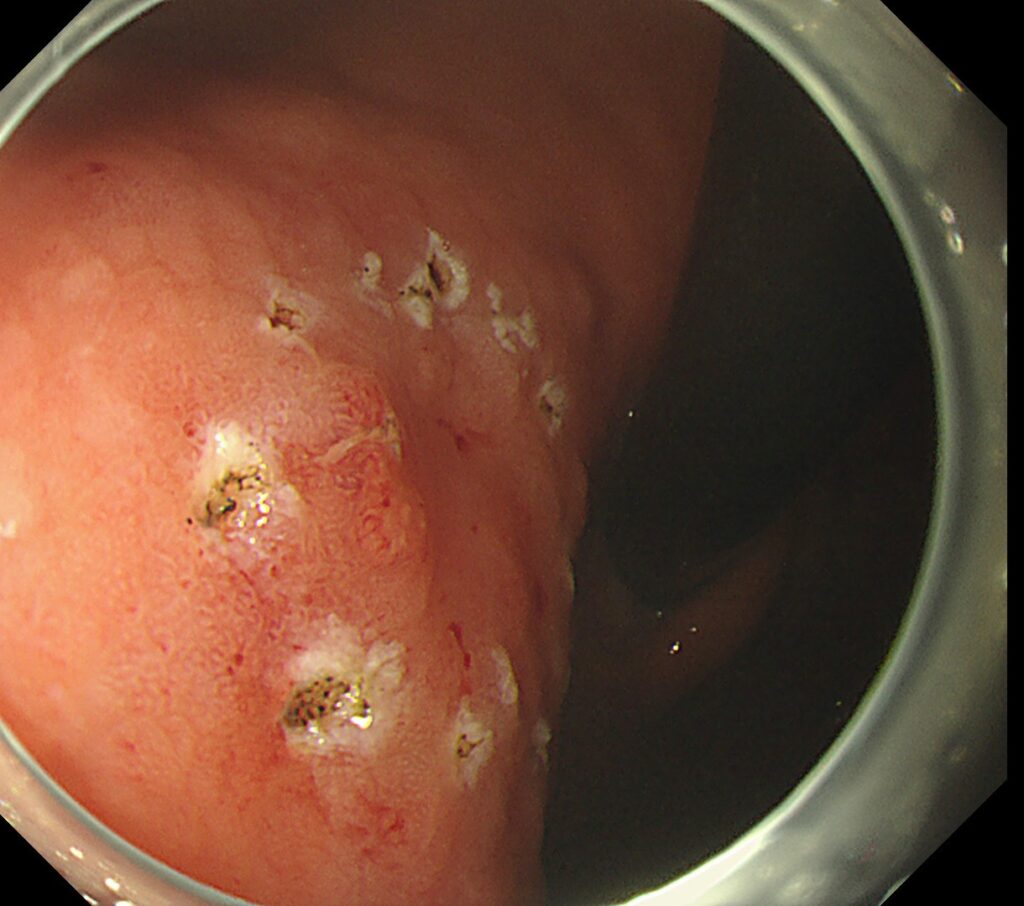

周辺マーキングを行い、剥離開始しました。

予想通り、筋層と病変が強固に癒着し、通電するスペースがごくわずかしかない状況。なお、使用した局注はもちろん、ヒアルロン酸です。

剥離に関しては、筋層を損傷しないように、繊維を1本ずつ剥がしていくように進めていきます。

そこで出番は、オリンパスのフックナイフ。写真のごとく、繊維引っ掛けて切っていくデバイスとなります。

筋層と線維化領域を見極めないと、穴が空き緊急手術となる場面ですが、豊富な経験と臨床的嗅覚を活かし、病変切除成功となっております。

潰瘍底をみれば、エキスパートの先生であれば、察すると思いますが、強烈な線維化(癒着)症例でした。

切除時間は、28分です。(一般病院では1時間以上かかると思います)